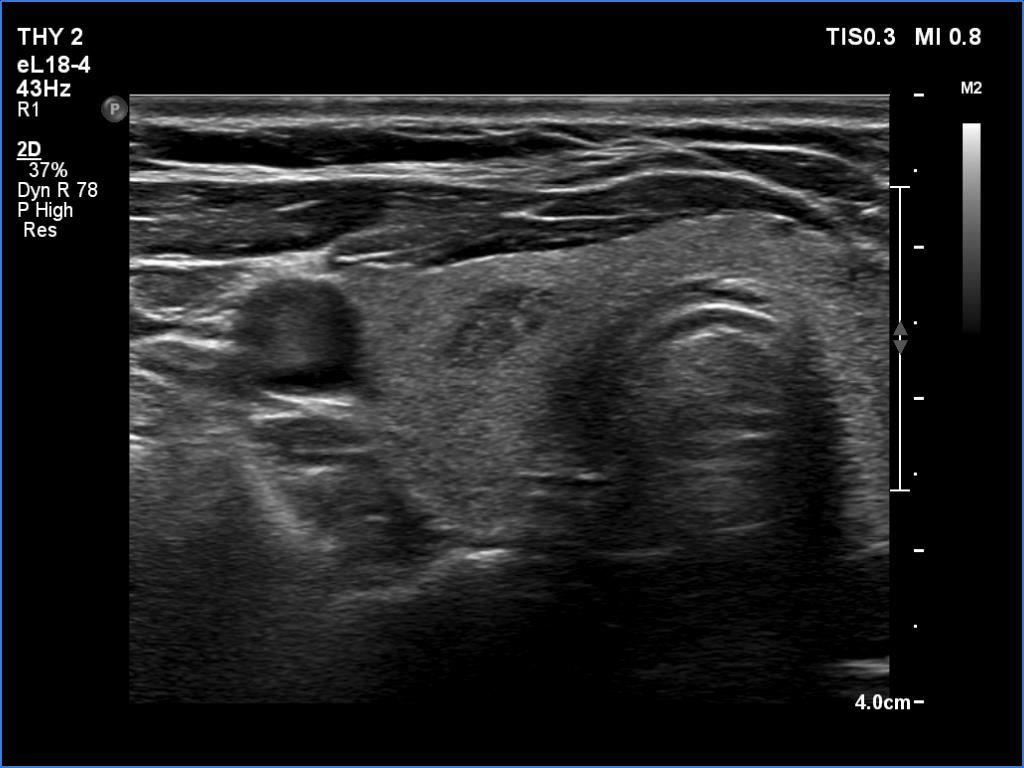

Ultrasonography. The thyroid was echonormal. There were several minimally hypoechoic discrete lesions in both lobes. Corresponding to the palpable nodule, a mixed, solid-cystic nodule was found which had spongiform areas. The solid part was minimally/moderately hypoechoic. The lesion did not show halo and presented neither intranodular nor perinodular blood flow.

Although the nodule belongs indeed to TIRADS 4 lesions, the risk of malignancy is practically zero in nodules with such presentation. This is probably an evolving spongiform cyst. A significant proportion of solid area has been already disappeared.